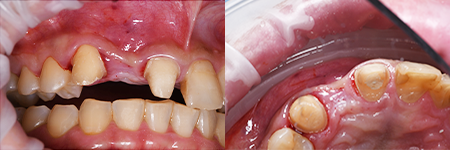

症例1. 根面被覆

| 歯茎が下がってしまっています。 | 歯茎を移植して覆った状態です。 汚れが付きにくくなりました。 |